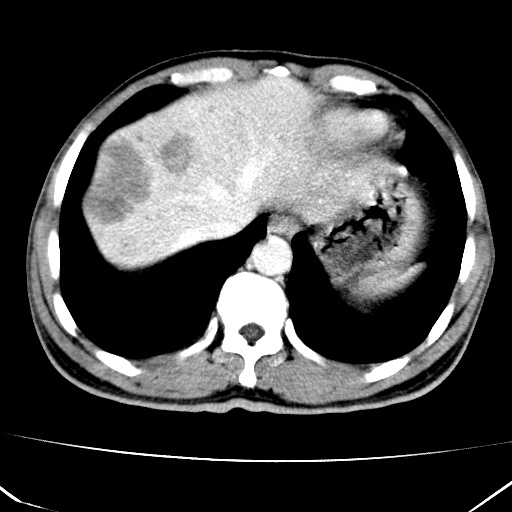

肝脏多发类圆形低密度影,考虑肝脏转移瘤,肝胃韧带一淋巴结肿大,原发?胃癌?

考虑胃癌肝脏转移可能性大。

考虑胃癌并肝脏及腹膜后淋巴结转移;不排除淋巴瘤。

肝内转移瘤,腹腔及腹膜后淋巴结转移。